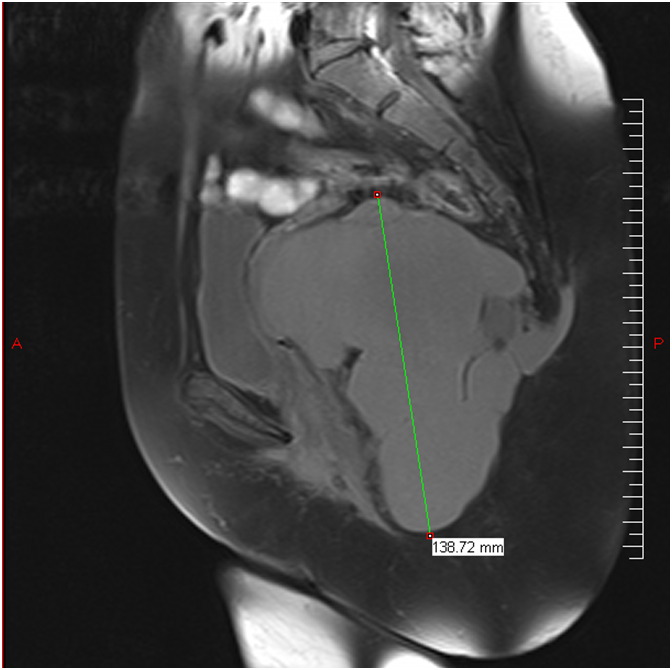

Le Scanner puis l’IRM (fig1) avaient montrer une masse retro rectale de 14 cm sur son grand axe d’allure kystique lobulée multiloculaire: déviant: rectum, vessie, utérus, vagin et allant jusqu’à l’aire Ischio anale à droite et en retro coccygien et qui serait un Hamartome ; La recto coloscopie montrait une compression extrinsèque du versant droit du rectum.

Figure1)IRM = Tumeur de 14 cm allant jusqu'a la région ischio anale et en retro-coccygien